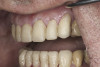

(9.) Preoperative right lateral, closed view.

Figure 9

(10.) Preoperative anterior, closed view. Note the end-to-end occlusion of the anterior teeth and the wear on the incisors and centrals resulting in no anterior or canine guidance.

Figure 10